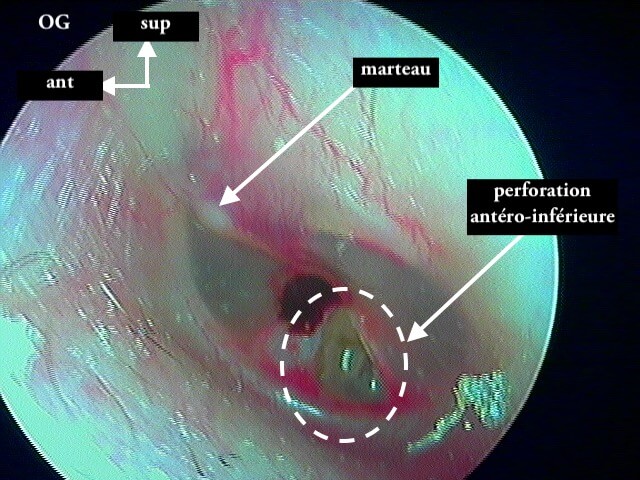

3/4 post otitique récente

Ici une otite séromuqueuse gauche perforée cicatrisée à 1 mois (cicatrice inférieure)

Une otite séromuqueuse droite perforée (et non otite moyenne aiguë)